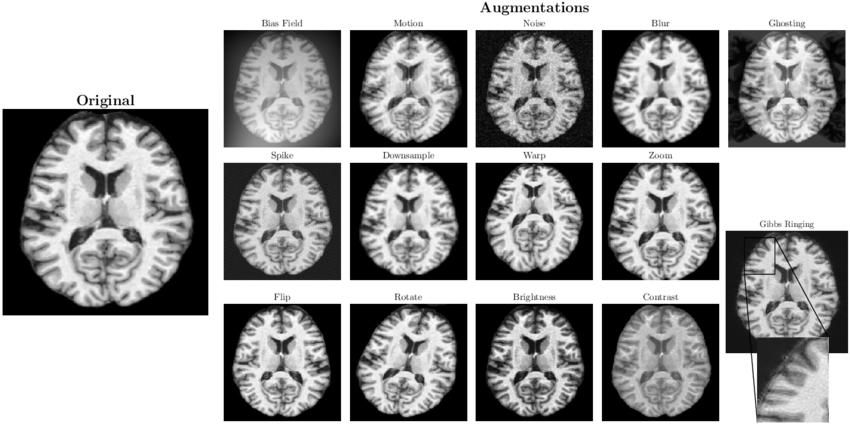

Augmentations

In machine learning, the performance and generalization ability of a model are heavily dependent on the quality and quantity of the training data. Therefore, data augmentation is a powerful technique used to artificially increase the size and diversity of a training dataset by creating modified, yet plausible, versions of existing data. It’s one of the most effective strategies to combat overfitting and improve model robustness, especially when the amount of available training data is limited.

The core idea is to apply a series of random (but realistic) transformations to the training images. For a model, an image of a cat that is slightly rotated or flipped horizontally is still an image of a cat. By exposing the model to these variations, it learns to recognize the core features of the object, regardless of its orientation, position, or lighting conditions.

Common augmentation techniques for images include:

- Geometric transformations:

- Rotation - rotates the image by a random angle.

- Flipping - flips the image horizontally, vertically or horizontally and vertically.

- Cropping - randomly crops a section of the image.

- Scaling - zooms in or out on the image.

- Translation - shifts the image horizontally or vertically.

- Color and photometric transformations:

- Brightness/contrast adjustment - randomly alter the brightness or contrast.

- Hue/saturation jitter - changes the color properties of the image.

- Additive noise - adds random noise to the image pixels.

By applying these augmentations, it is possible to create a virtually infinite stream of unique training examples from a finite dataset, forcing the model to learn more general and invariant features. This ultimately leads to a more robust model that performs better on new, unseen data.

Example augmentations. Images source:

deepmriprep: Voxel-based

Morphometry (VBM) Preprocessing via Deep Neural Networks